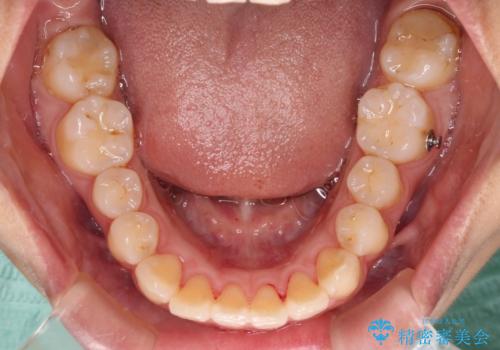

- 前方に傾斜した上下の前歯を気にして来院された患者様です。

唇の閉じにくさや横顔のシルエットが気になるような突出感ではなかったため、インビザラインを用いて、歯列の遠心移動とIPR(歯と歯の間を削る)により前歯の傾斜を改善していくこととしました。

スムーズに終了すると思われましたが、インビザライン矯正独特の奥歯が咬み合わない状態が続き、更には遠方へ転居されたこともあり、治療期間は長引いてしまいました。